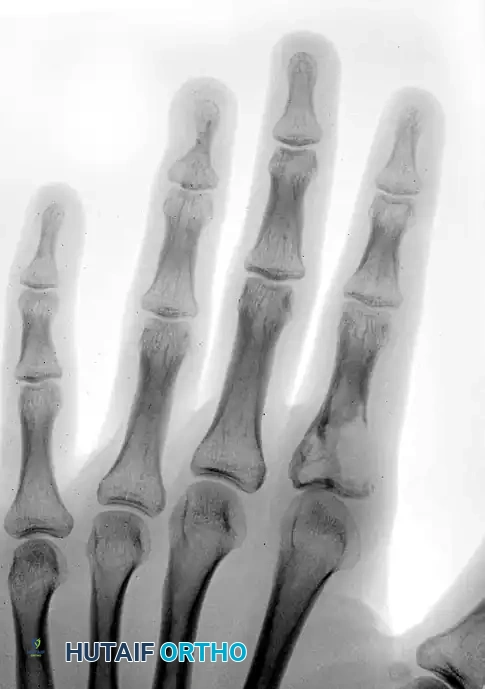

Image

FIGURE 77-13: Radiograph demonstrating multiple enchondromas with significant cortical thinning and expansile remodeling of the phalanges, characteristic of Ollier disease.

Radiographically, they appear as well-circumscribed, central radiolucent lesions within the metaphysis or diaphysis of the phalanges or metacarpals. They often exhibit endosteal scalloping and may contain stippled or punctate calcifications (the "rings and arcs" pattern of chondroid matrix).